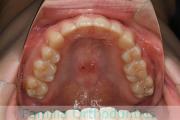

- ≫治療前

上顎

下顎

前歯の関係など

右側

正面

左側